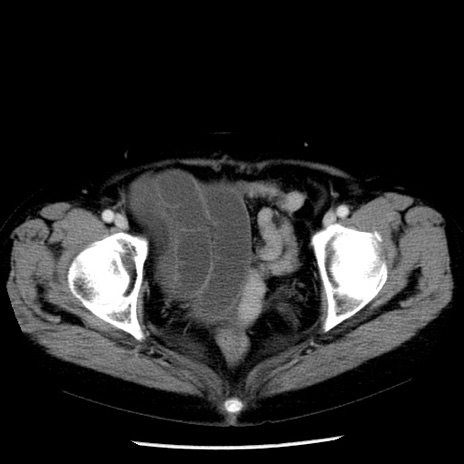

症例13(横断像)

【症例】70歳代女性

【主訴】腹痛、嘔吐

【現病歴】15時間程前(昨晩)より腹痛あり。今朝になっても症状の改善なく、嘔吐あり。腹痛も増悪あり、救急外来受診。

【既往歴】子宮癌全摘術後

【身体所見】意識清明、BP 121/72mmHg、P 74bpm、SpO2 100%(RA)、腹部:平坦・軟、腸雑音ほぼ聴取せず。下腹部・心窩部・臍左上に圧痛あり。反跳痛なし。

【データ】WBC 10600、CRP 0.15